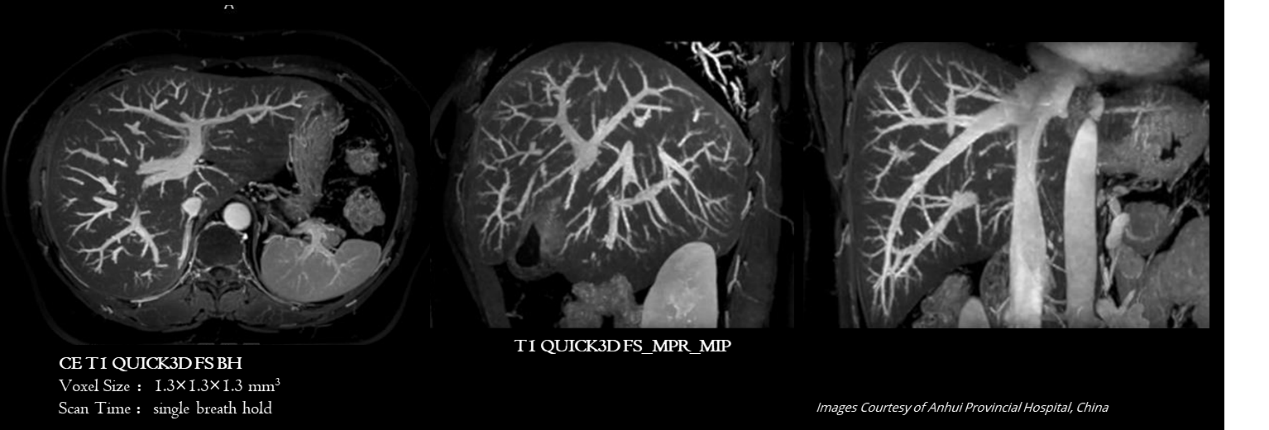

磁共振腹部成像

实验和研究,包括磁共振腹部成像的技术开发、序列优化、临床应用等。